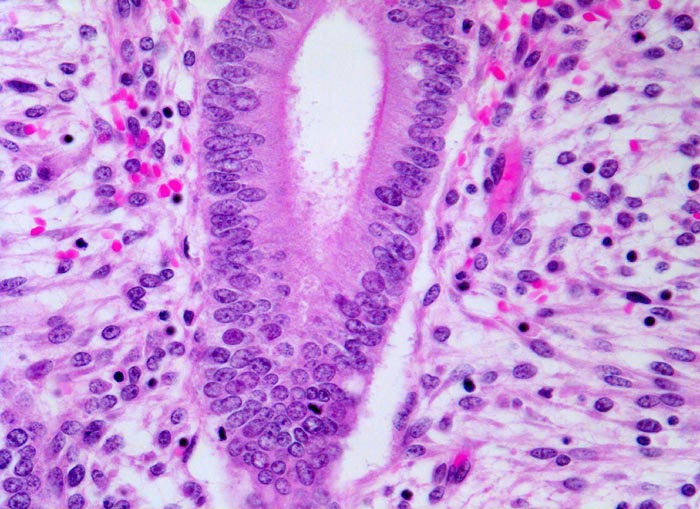

• Tumordrüsen ausgekleidet von mehrreihig angeordneten Tumorzellen mit hyperchromatischen polymorphen längsovalen Tumorzellkernen mit zahlreichen Mitosen. Die Morphologie der Tumordrüsen erinnert an proliferatives Endometrium.

Endometrioide Karzinome bestehen aus tubulären Drüsen, welche von einem mehrreihigen Epithel ausgekleidet werden. Schleim ist meist nicht oder nur apikal in den Zellen vorhanden. Die Ausdehnung der soliden Areale und die zytologischen Atypien bestimmen den Differenzierungsgrad (low-grade versus high-grade). Metaplastisches Plattenepithel findet sich häufig in endometrioiden Karzinomen und hilft bei der Abgrenzung von anderen Subtypen. Das endometrioide Karzinom kann sich innerhalb von Adenomyoseherden im Myometrium entwickeln (> 4482). In diesen Fällen kann die Bestimmung der Infiltrationstiefe erschwert sein.